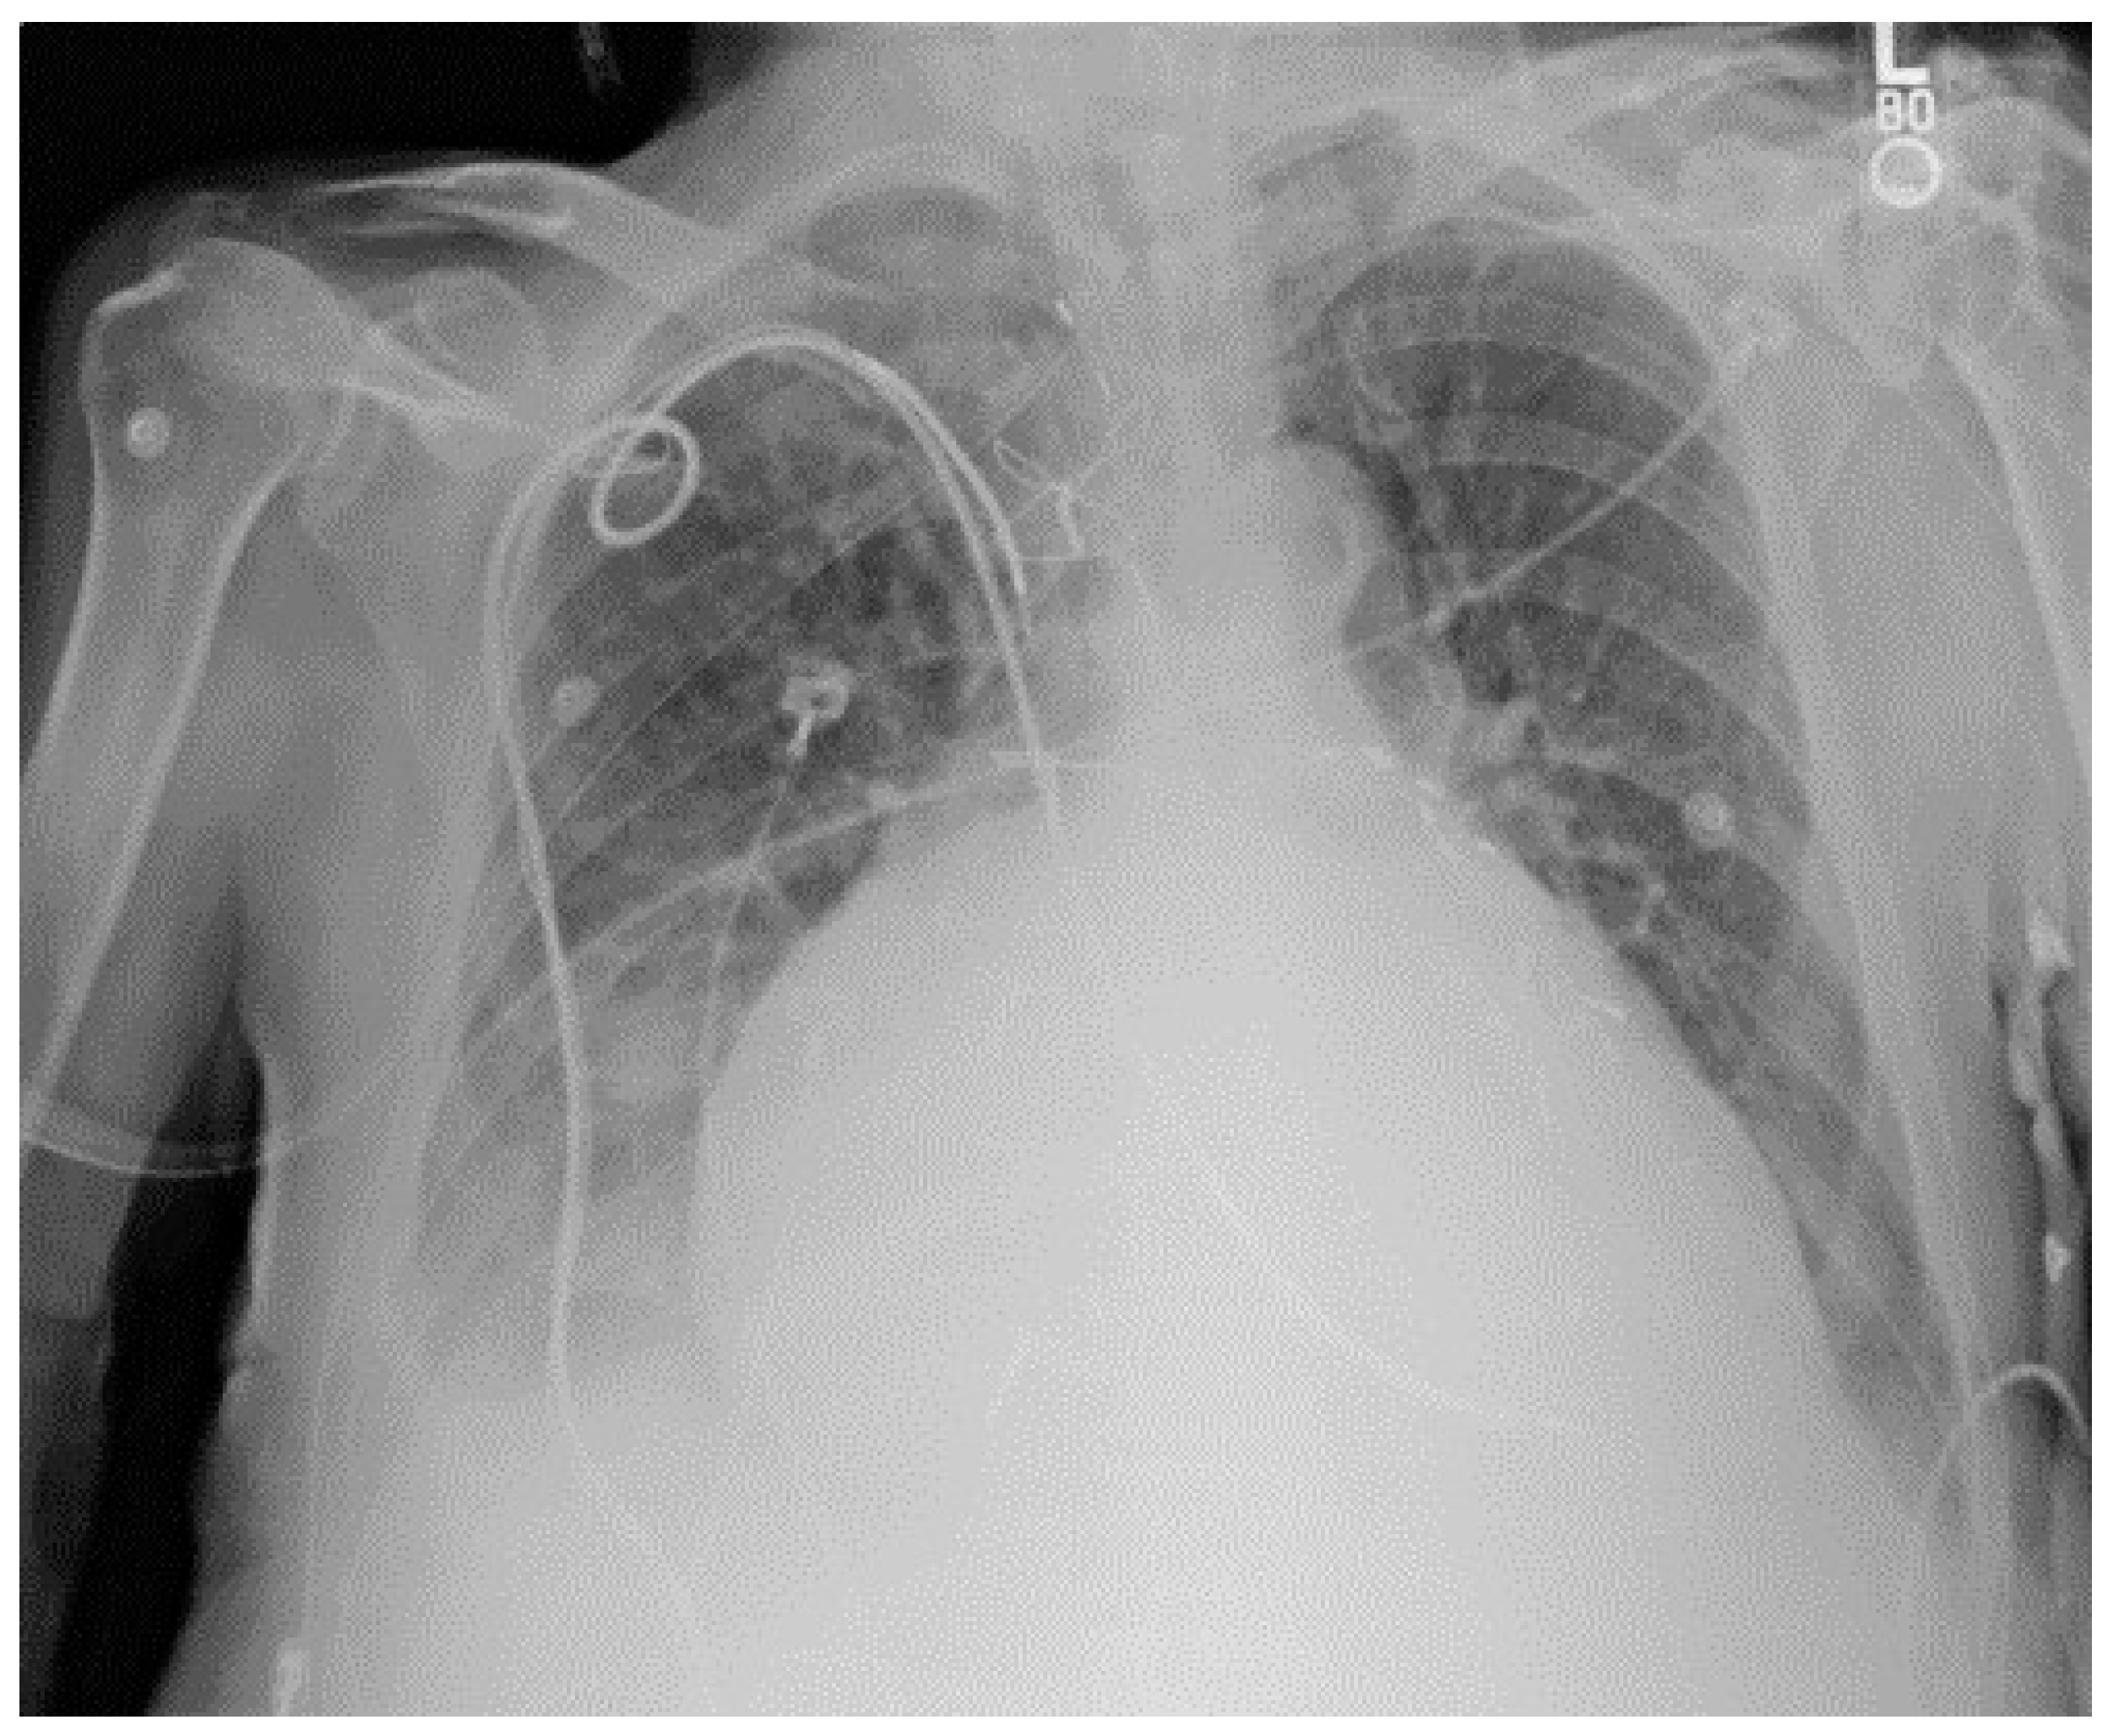

For traditional USM method, we have chosen different kernel size for Gaussian filter ( 15 × 15 , 19 × 19 , and 23 × 23 separately). Figure 3 shows a CXR from the portable CXRs database. The contrast of line structure in the spine and heart area is limited, and it is hard to find the tips of ET and NT. Enhancement is necessary for ICU CXR. Figure 4 shows the enhanced results obtained by using traditional USM. The EMEE value for the original image was 0.491. After enhancement, the EMEE values were improved to 0.841 (Figure 4c), 0.980 (Figure 4f), and 1.106 (Figure 4i), corresponding to the Gaussian kernel size of 15 × 15 , 19 × 19 , and 23 × 23 , respectively. Although, the EMEE values were improved, some important edge information still did not show clearly in the image, especially when the kernel size was smaller. When the kernel size of Gaussian increased, the noise and the edges were enhanced simultaneously. As a result, Figure 4c,f,i did not have high contrast, which was predictable based on the properties of the traditional USM algorithm.

Figure 4. CXR enhancement by use of traditional USM model. (a,d,g) were the smoothed images by use of 15 × 15 , 19 × 19 , 23 × 23 Gaussian kernel, respectively; (b,e,h) were the corresponding Unsharp masks to (a,d,g); (c,f,i) were the corresponding enhanced images.